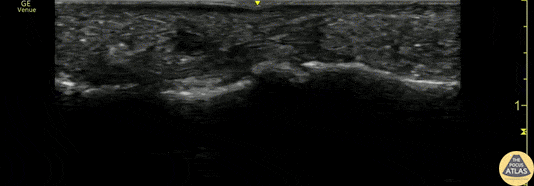

A 50s M presented with atraumatic finger pain/swelling x2 weeks. On exam, he had focal swelling localized the volar aspect of the ring finger over the proximal phalanx, without fusiform edema/erythema or any limitation of ROM. POCUS showed a small fluid collection adjacent to the flexor tendon. The flexor tendon is shown in long axis, with linear fibers seen just superficial to the bone cortex, and then is seen in short axis. The hypoechoic area superficial to the tendon represents the fluid collection. As the patient had intact ROM and no signs of infection, he was splinted and will follow up for a recheck of tendonitis. Kristy Karkula, PA and Dr. Ruth Foss Denver Health Medical Center